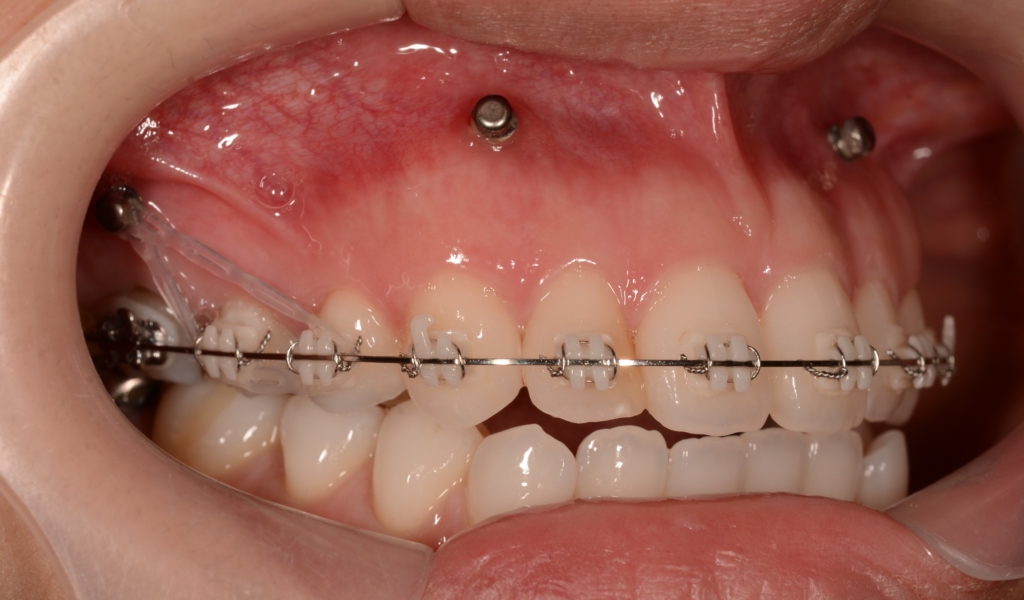

上の歯列がきれいに並んで、アンカースクリューを植立する目途がついたので、上顎の口蓋正中部、臼歯部と前歯部の頬側辺りにアンカースクリューを植立しました。(計6本)

奥歯の圧下による下顎の反時計回りの回転を狙っています

前歯部の噛み合わせに目途が付いた時点で、下の歯にも装置を付けて、合わせて治療を進めます。